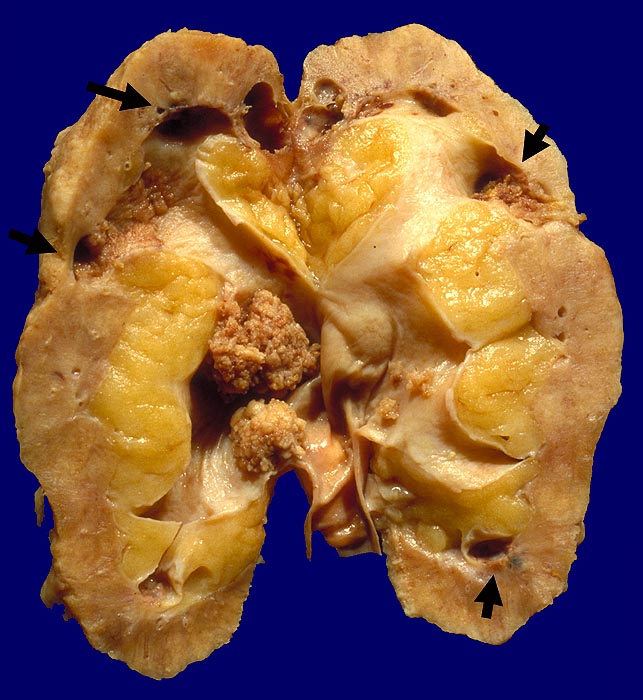

PathoPic ID 1588 - Analgetika-Nephropathie: Nierenbeckenkarzinom.

Analgetika-Nephropathie: Nierenbeckenkarzinom.

Multizentrisches polypöses Nierenbeckenkarzinom. Auf der Schnittfläche mehrere

►

Papillennekrosen.